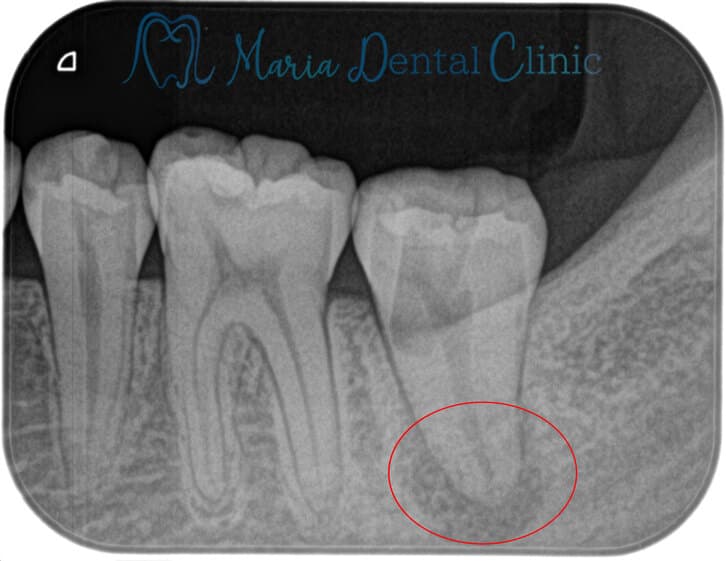

穿孔修復・パーフォレーションリペア|他院での偶発トラブルに対応したケース

| 主訴 | 左下の歯の痛みを訴え他院にて治療後、左下7番の歯肉(歯ぐき)が大きく腫れてしまった |

|---|---|

| 治療内容 | 再根管治療|精密根管治療 |

| 治療期間 | 1週間 |

| 治療費用 | 176,000円(税込)(穿孔修復代も含む) |

| リスク・副作用 | ・精密根管治療はすべて自費の治療になります。 ・根管治療終了後には術後性疼痛がある場合があります。 ・根管治療が予後不良の場合は歯根端切除術を行う必要があります。 |